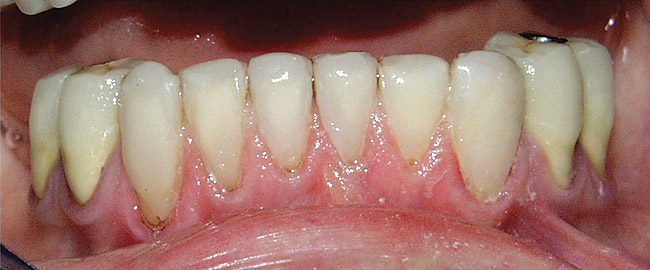

Aging

Tooth surface loss and tooth wear occur naturally with age, beginning even before the tooth reaches the occlusal plane.3,42 During the functional life of a tooth, cusps flatten, wear facets develop, enamel volume is lost from the tooth surfaces, and dentin is exposed. With the increased longevity of the human population, increased retention of teeth along with gingival recession gives rise to more tooth surface exposure, thus greater potential for formation of non-carious lesions. The elderly population whose teeth are retained for longer periods of time and who have increased exposure of root surfaces may be at higher risk of developing erosive lesions.43

Figure  6  Erosion and abrasion in a xerostomic patient with Sjögren’s syndrome.

Figure 6